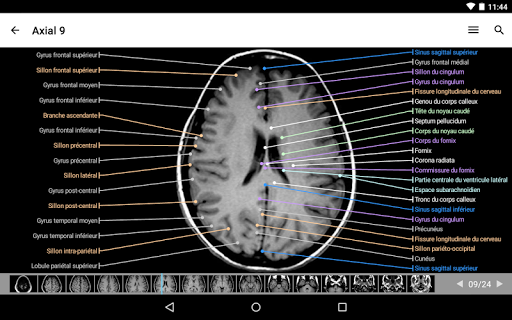

IMAIOS e-Anatomy es un atlas de anatomía humana para médicos, radiólogos, estudiantes de medicina y técnicos en radiología. Echa un vistazo a más de 26 000 imágenes médicas y anatómicas de forma gratuita antes de suscribirte a nuestro detallado atlas de anatomía humana.

e-Anatomy se basa en el galardonado atlas en línea IMAIOS e-Anatomy. Lleva contigo la referencia más completa de anatomía humana, dondequiera que vayas, en tu dispositivo móvil o tableta.

e-Anatomy tiene más de 26 000 imágenes que contienen series de imágenes en vistas axiales, coronales y sagitales, así como radiografías, angiografías, imágenes de disección, gráficos anatómicos e ilustraciones. Todas las imágenes médicas fueron etiquetadas cuidadosamente, más de 967 000 etiquetas disponibles en 12 idiomas, incluida la Terminologia Anatomica latina.

- Desplácese por los conjuntos de imágenes arrastrando el dedo

- Acerque y aleje el zoom

- Toque las etiquetas para mostrar las estructuras anatómicas

- Cambie de idioma con solo tocar un botón